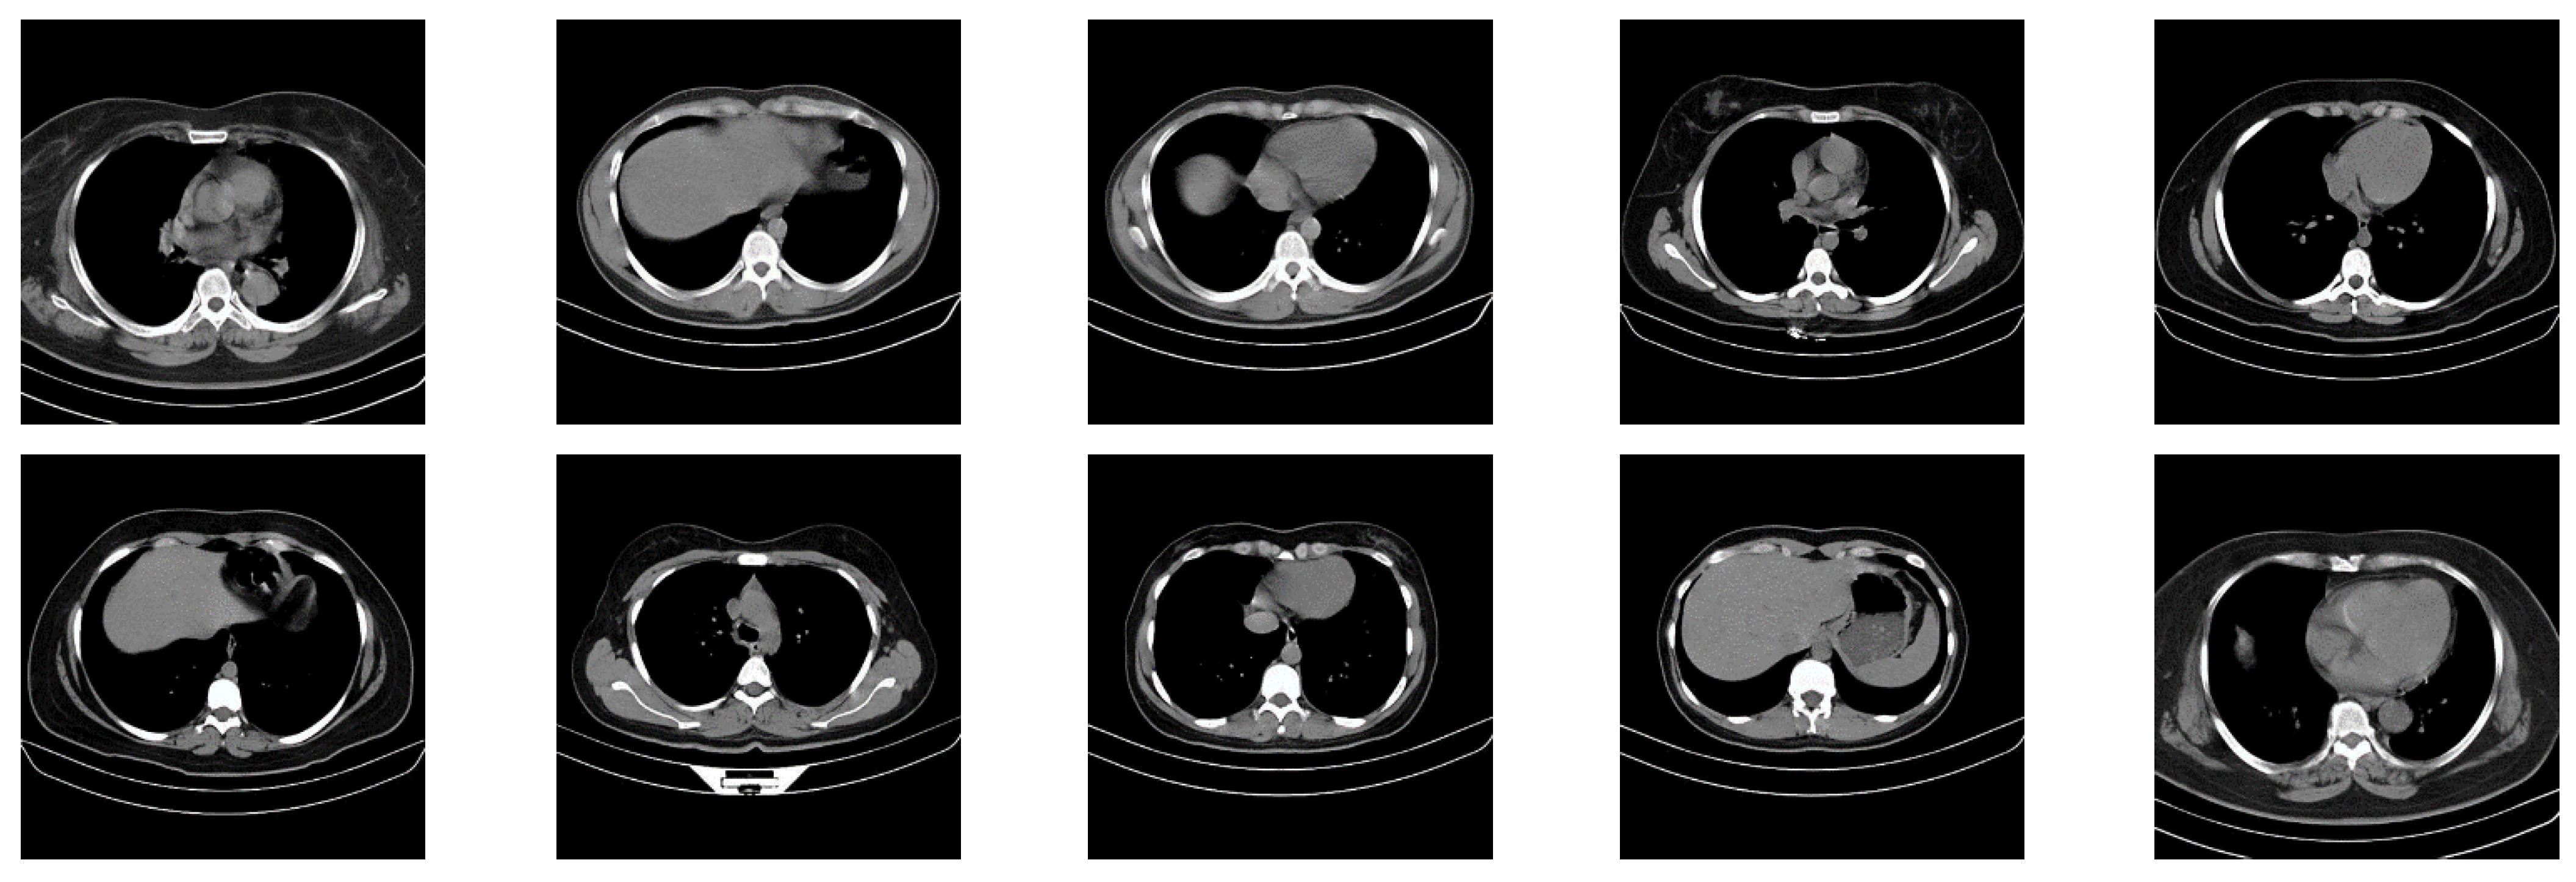

In this paper, in order to evaluate the proposed cryptographic method, multiple medical images and benchmarks have been adopted. The images tested in this section contain a variety of standard benchmark images and medical images including CT and X-ray. In Figure 11, 10 images of standard benchmarks for conducting experiments are displayed. Also, shown in Figure 12 are X-ray images of COVID-19 patients. Finally, 10 CT images of patients with COVID-19 are used for the final tests, as shown in Figure 13.

CT images used in the proposed method.